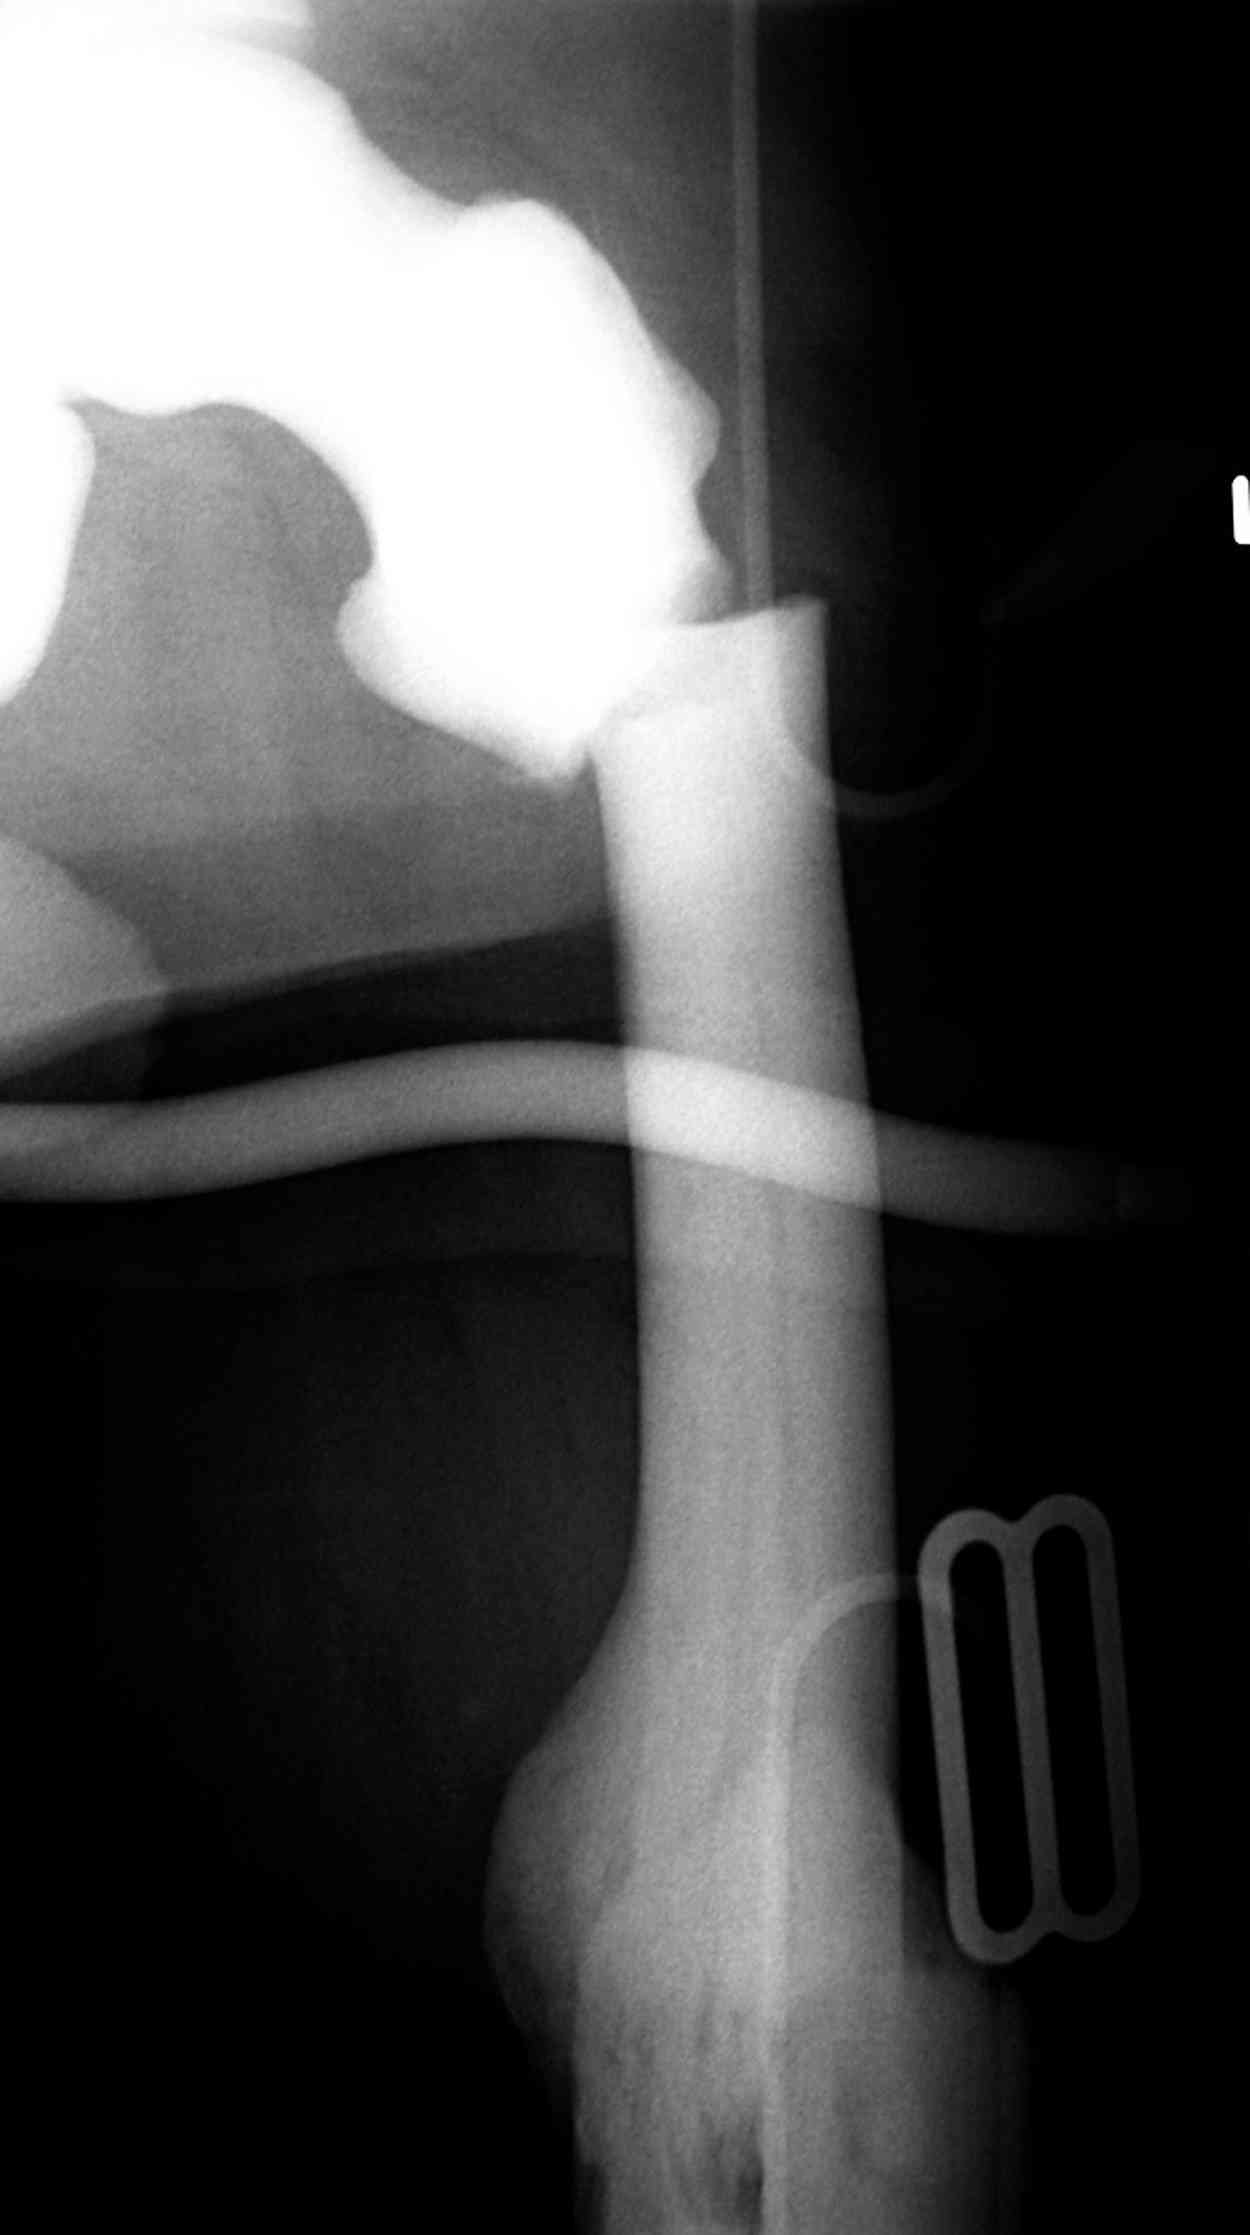

Остеопетроз характеризуется болями в костях, а на ренгене следы множественных несращении длинных трубчатых костей и “белая-мелоподобная” кость.

“При лечении переломов у больных с остеопетрозом (в прошлом году был случай) необходимо быть готовым к длительным операциям из-за трудности

обработки традиционными методами "мраморной" кости, иметь в наличие достаточное количество свежих острых инстументов и персонала при необходимости замены (были случаи отстрочки операции на следующий день из-за физической усталости персонала), и надо избежать особо трудоемких операции как интрамедуллярное сверление”.

слайды из прошлегодного случая.